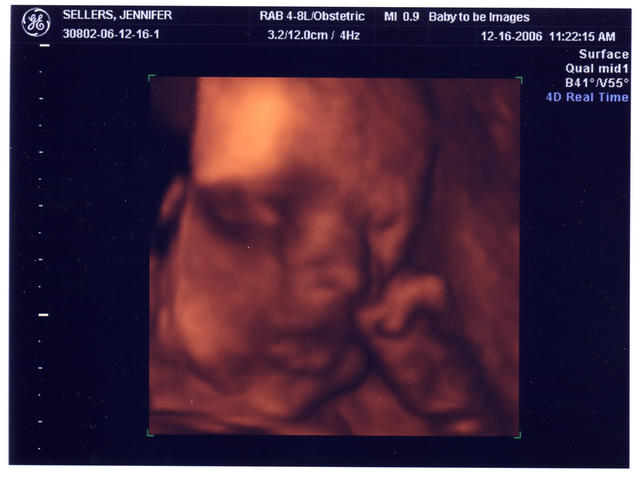

After returning from Jamaica, we went to Baby To Be and had a 3D ultrasound of our little girl. We got a DVD and some pictures of it. Here's a picture of her face and her left hand.

and here's a picture from the side. I think she has Jen's nose. And better yet, watch this 6 minute video clip of the 3D ultrasound (requires Quicktime to view).